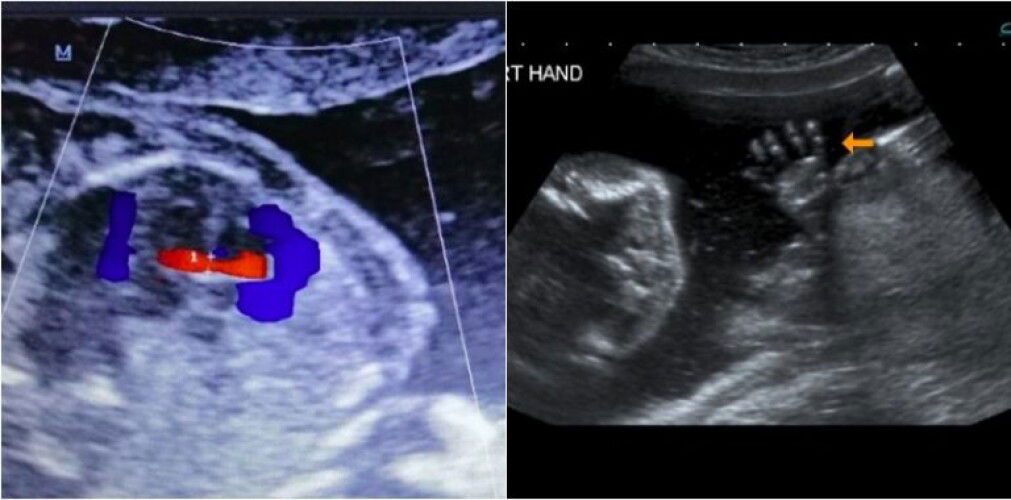

When is the best week to the detail scan?

More info: https://my.theasianparent.com/detail-scan